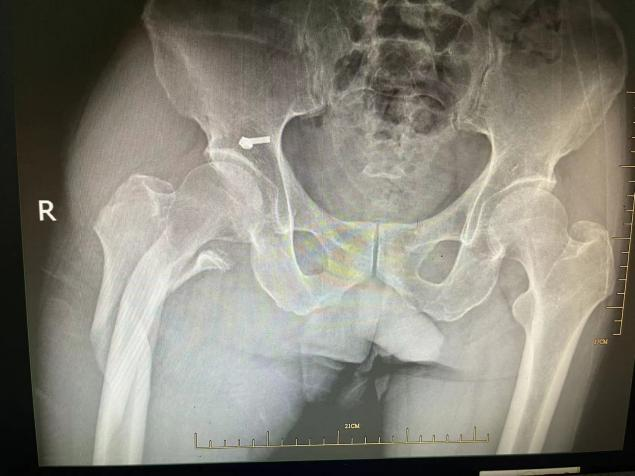

病例介紹 居住在椒江區(qū)的陳大爺70多歲了,患有帕金森綜合征20多年,慢性肺部感染約10年。一年前,陳大爺不慎跌倒導致右股骨粉碎性骨折,入住臺州市中醫(yī)院骨傷科。 病案分析 接診醫(yī)生我院骨傷科副主任中醫(yī)師徐榮敏認為,此類股骨上端骨折的病人最好的治療方案是手術。 如果保守治療,眾多并發(fā)癥是導致患者近期死亡的主要因素,雖然骨科手術并不是太難,但是患者平時2至4小時就需要服用抗帕金森藥物和吸痰,平時主要靠兒子照顧,藥效一過,痰就咳不出,全身抖動厲害。麻醉、手術、護理也各有難度,疊加起來就是難上加難,手術風險較大。 選擇手術還是保守治療,需要患者及其家屬做出選擇。 抉擇過程 在得知手術風險時,患者及其家屬也有過遲疑,考慮是否轉上級醫(yī)院治療。 但李大爺慶幸了自己的第一次抉擇,李大爺說自己幾年前在別家醫(yī)院ICU宣告治療無效回家后,后來到臺州市中醫(yī)院呼吸科才治療好的! 這次面臨著第二次抉擇,大爺還是相信臺州市中醫(yī)院!選擇手術! 手術經過 經過呼吸科、神經內科、心內科、手術室、麻醉科、ICU等科室的聯(lián)合會診,骨傷科徐榮敏醫(yī)師、陳國軍醫(yī)師等制定了詳細的手術計劃,麻醉科主任聶運明、麻醉醫(yī)生王曉等在術前也制定了詳細的麻醉計劃和應急準備,包括麻醉藥物控制劑量、術中鼻飼給予抗帕金森綜合征的藥物等。 幸運地是,手術在2小時之內順利完成,術后ICU密切觀察,第二天即回骨傷科病房。 術后護理 在常規(guī)中西醫(yī)結合治療的同時,護士長蘇韓、責任護士錢淼淼等護理同仁為其制定了細致周詳的護理計劃。在拍背、吸痰、功能鍛練等常規(guī)護理基礎上,運用辨證施護原則,因人因病而異,綜合運用耳穴埋豆、腕踝針、穴位貼敷、隔物灸等中醫(yī)適宜技術,避免了壓力性損傷、下肢深靜脈血栓、肺栓塞等并發(fā)癥的發(fā)生,安全的度過了圍手術期。 幾天后考慮患者平時患有慢性肺部感染,予轉入呼吸科。經過約1月的治療護理,李大爺恢復良好后出院! 一年后大爺的骨折愈合良好。 據徐榮敏醫(yī)師介紹,在骨傷科像這樣的老年病人其實有很多,患者往往有高血壓、糖尿病、冠心病、腦梗死、帕金森綜合征、慢性阻塞性肺疾病、腎功能不全等基礎疾病。骨傷科作為浙江省“十三五”中醫(yī)藥重點學科,設有重點學科研究室,對治療老年骨傷科疾病有獨特的研究和良好的效果。 脊柱創(chuàng)傷骨傷科為浙江省中醫(yī)重點??啤⑴_州市重點學科、上海中醫(yī)藥大學“石筱山傷科”聯(lián)盟單位。 學科特色:繼承傳統(tǒng)中醫(yī)骨傷特色治療理念,與時俱進,不斷吸收國內外當代先進骨科治療技術,中西醫(yī)結合,注重微創(chuàng),安全有效,精心護理,快速康復。 診療專長:四肢骨折脫位的手法復位加夾板(石膏)固定或手術治療;脊柱骨折的切開復位內固定;骨質疏松癥、風濕骨病、脊柱腰腿痛、骨關節(jié)炎的中西醫(yī)結合特色治療;軟組織疾患的針刀和體外沖擊波治療,骨質疏松性脊柱骨折的骨水泥成形術;頸腰椎間盤突出癥、椎管狹窄癥的椎間孔鏡手術和椎間融合手術,肩髖膝人工關節(jié)置換術,肩膝關節(jié)疾病的關節(jié)鏡手術,穴位貼敷等中醫(yī)特色治療護理技術,老年病人術后快速康復。 人才隊伍 :高級職稱5人,碩士研究生4人,多人擔任國家與省市級學會委員、副主委,主持市廳級課題多項,撰寫論文幾十篇,學術專著多部。 科室理念:中西結合,發(fā)揮特色,無痛少痛,快速康復。 聯(lián)系電話:0576-88825725